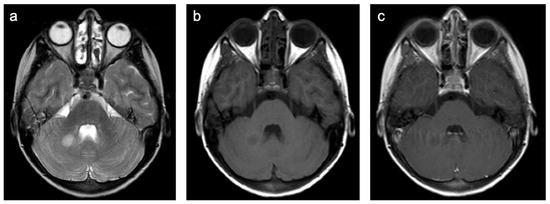

Group 1 consisted of 40 patients. Twenty-five (63%) patients suffered from multiple sclerosis (MS) and nine (23%) from acute demyelinating encephalomyelitis (ADEM). Three patients were diagnosed with a clinically isolated syndrome, one with limbic encephalitis, one with Rasmussen’s encephalitis, and one with vasculitis. Representative cases are shown in Figure 3. A total of 63% of patients were female and the mean age was 14.0 years (min 2.6 years; max 18.4 years). All but one patient were examined with contrast-enhanced MRI and 44% of those examinations showed at least one enhancing lesion. WMSAs were localized supratentorial in 65% of patients and supra- and infratentorial in 35% of patients. There were no isolated infratentorial lesions. In total, 90% of patients had multifocal WMSAs.

Figure 3. Representative case “Autoimmune disorders”: MS. FLAIR (a), T1W pre- and post-contrast (b,c) sequences. Fifteen-year-old girl diagnosed with MS. MRI shows characteristic ovoid/round lesions with asymmetric distribution abutting the lateral ventricles (periventricular) and touching the cortex (juxtacortical) [19] (a). Contrast-enhancing lesions in T1W post-contrast sequences are considered markers of blood–brain barrier breakdown (c).